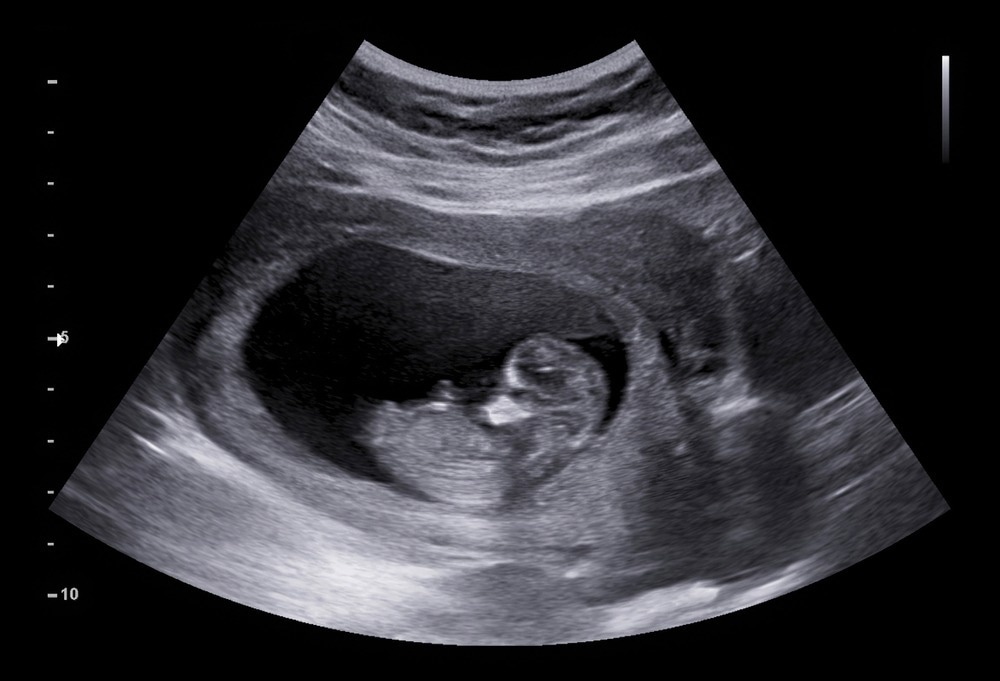

Image Credit: AePatt Journey/Shutterstock.com

The first trimester is the period from conception to 12 weeks, and during this time, the fertilized egg will develop from a cluster of cells to a fetus that expresses features. In the 1st month, a face will form with a mouth, jaw, throat, and dark space for eyes. In the second month, arms and legs form tiny buds, and the neural tube develops more. Towards the end of the 1st trimester, the limbs are fully formed, and the fetus can move its mouth and open its fists. The circulatory and digestive are working; the fetus is 4 inches long and weighs 1 ounce.